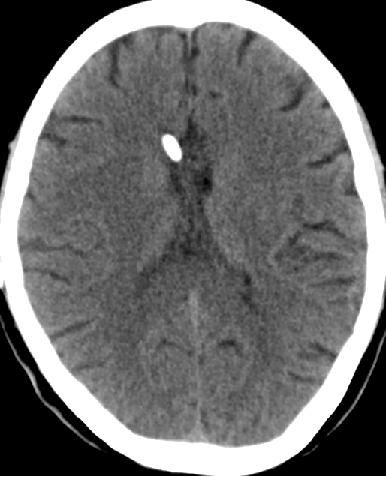

2013-8-8 CT

2013-8-7 脑室腹腔分流术,初压130

2013-8-8 仍诉头痛

2013-8-10 腰穿测压150mmH2O